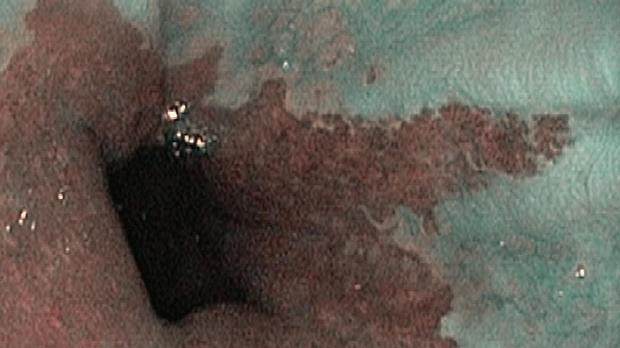

Появление ультратонких гастроскопов с высоким разрешением и технологией NBI (оптического узкоспектрального режима) компания OLYMPUS сделала возможной гастроскопию экспертного уровня под местной анестезией, без наркозных рисков.

Ультратонкие гастроскопы GIF-XP170N и GIF-XP190N с параметром оптики Close Focus, который позволяет приближаться к слизистой на минимальную глубину резкости до 2 мм, обеспечивают качество изображения, сопоставимое с аппаратами экспертного класса.

В Центре Экспертной Эндоскопии, г. Симферополь с июня 2018 с помощью этих эндоскопов выполнено более 1000 эндоскопических исследований, с полным соблюдением критериев качества ESGE. Среднее время исследования составило 14мин. 51с. Все исследования выполнялись с предварительной подготовкой желудка, применением водяной помпы и СО2-инсуффлятора, фото- и видеодокументацией.

Использование в ежедневной рутинной практике современных ультратонких эндоскопов высокого разрешения с технологией оптического узкоспектрального режима (NBI® OLYMPUS™) под местной анестезией позволило полностью обеспечить соответствие критериям качества выполнения эндоскопических исследований, определенным ESGE. Данный метод комфортен для пациента под местной анестезией, безопасен, является простой и удобной альтернативой ЭГДС под седацией, что особенно важно в амбулаторных условиях.